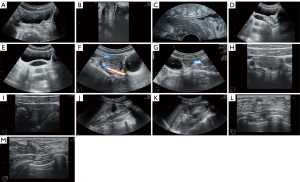

A 21-year-old patient with a female phenotype was admitted to our hospital for primary amenorrhea. Gynecological examination of the external genitalia showed a female juvenile vulva. The vagina could accommodate the little finger, but the cervix could not be reached. No mass was palpated in the pelvic cavity. The patient’s breast size was normal, with relatively small nipples. The pubic and armpit hair was thin. The patient was then referred for a comprehensive sonographic examination, which was performed with the MMSS. The main findings were pooled as follows (Figure 1): (I) a pair of gonads suspected to be testicles, which were smaller than normal testicles, were detected in the upper pelvic cavity; however, ovotestes could not be definitively excluded; (II) under the guidance of sonography, catheterization was performed smoothly, followed by injection of normal saline into the internal reproductive tract. The internal reproductive tract was fully dilated and its dilatability was precisely measured; (III) the internal reproductive tract was inferred to be a blind vagina as it appeared to be a cord-like hypoechoic structure, with no characteristic contour of the uterus, cervix, or endometrium; and there was no fluid accumulation in the pelvic cavity during the process of SIS, which suggesting that the internal reproductive tract did not communicate with the pelvic cavity; (IV) no vaginal-urethral confluence, abnormal passages of the urogenital sinus (UGS), or hypospadias were noted; (V) bilateral breasts were well-developed; and (VI) no upper urinary system malformation or abnormalities of the adrenal glands were observed. A diagnosis of CAIS was suspected.

CAIS is a rare type of DSD characterized by maternally inherited or de novo mutations involving the androgen receptor. During embryonic development, differentiation of the bilateral Mullerian ducts into the fallopian tubes, uterus, and upper vagina, in which the UGS forms the lower segment of the vagina, is blunted (6,7). Verification of the vagina’s presence and determination of its dilatability, especially the length, is an important factor for deciding whether vaginoplasty, an operative treatment, should be given preference or not. By taking advantage of different frequency probes and multiple perspectives, we confirmed the existence of a blind vagina and obtained its length when it was fully dilated (approximately 14.0 cm). Vaginal dilatation, a non-invasive therapy, was subsequently recommended in this case. Moreover, exclusion of vaginal-urethral confluence, hypospadias, and other abnormal passages of the UGS aided in the differentiation of CAIS from other types of DSD, such as partial AIS or 46XX, DSD.

The gonads in this case of CAIS were actually testicles. Androgen produced by the testicles can be converted into estrogen in vivo, so the natural initiation of puberty can still be maintained (6). On the other hand, since undescended testes have a high probability of malignant transformation after puberty, gonadectomy in early adulthood is recommended (8). Therefore, the evaluation of the type and location of the gonads facilitates the determination of the opportunity and scope of surgery. Moreover, evaluation of the type of gonads can distinguish CAIS from Mayer-Rokitansky-Küster-Hauser syndrome, which also often presents with primordial uterus or blind vagina. Nonetheless, the gonads in the former condition are testicles, whereas in the latter, they are ovaries. Low-frequency sonography and superficial high-frequency sonography play different roles in the assessment of gonads. Low-frequency sonography focuses on the determination of location, while superficial high-frequency sonography has the advantage of observing structural details. Studies have shown that the location of gonads helps to identify their type, as undescended testes are predominantly located at the descending path of normal testicles. In CAIS, 35.7%, 48.2% and 16.1% of gonads are located at the pelvic, groin, and labia majora, respectively (7). By sequentially scanning these regions with low-frequency sonography, we found a pair of gonads in the upper pelvic cavity, which increased the possibility that the gonads were testicles.

Subsequently, detailed structural characterization with superficial high-frequency sonography demonstrated anatomical features that are consistent with undescended testes. The solid nodules in the gonads were consistent with the pathological findings, which might be related to the stagnation of testicular tissue development in a relatively primitive stage. Undescended testes should be differentiated from ovaries and ovotestes, which can be distinguished by location and internal structure (obtained by the MMSS). For women of reproductive age, the ovaries are generally fixed in the adnexal area with follicular structure. The ovotestes, which are composed of both ovarian and testicular tissues in different proportions, are often located at the position of the predominant gonadal type under normal circumstances (9). Ovarian tissue might envelop the testicular tissue in a circular fashion within the ovotestes (10), or the 2 tissues might be located at both poles and connected with each other. Based on the location and structural details, the gonads in this case were suspected to be testicles, but ovotestes could not be completely excluded.